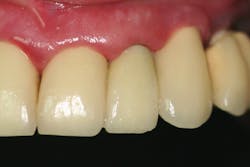

- Treatment plan: Extraction/immediate implant placement with nonfunctional provisional

The patient related to our office that he had absolutely no postoperative discomfort, no prosthesis complications, and was very impressed by the entire experience as he had a different outcome for his previous implant tooth replacements.Disclosures or conflicts of interest: Dr. Miller has a financial relationship with Ditron Dental USA. Products mentioned are used in the regular course of practice.